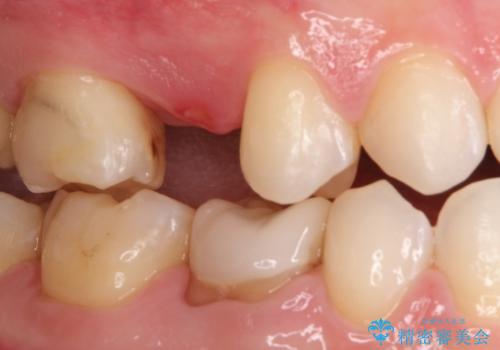

隙間が気になる。審美性の高いインプラント治療

- 欠損歯があり、隙間があることを主訴に来院されました。

術前に矯正治療(インビザライン)を行いインプラントにて欠損補綴を行なっております。

術前に矯正治療を行うことで適正な位置でのインプラント治療が行えました。